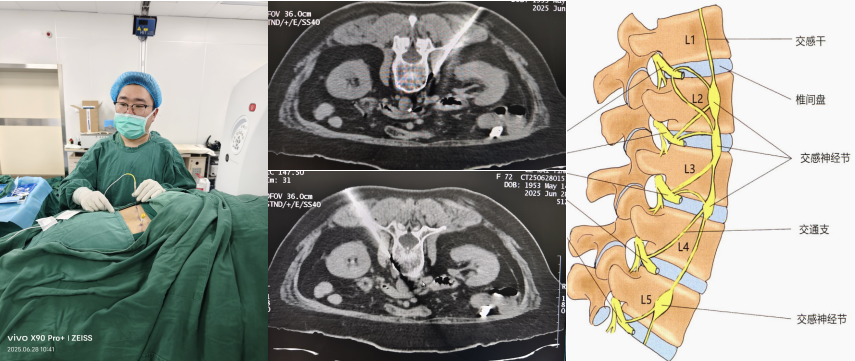

6月28日上午,乐奶奶腹腔镜下胃穿孔修补术后的第三天,疼痛科蔡继珩副主任医师在CT和B超的双重引导下,采用局部麻醉的方法精准地将射频针穿刺到乐奶奶的交感神经节部位,通过高电压90度左右的射频治疗温度,精准毁损其L2椎体下缘的腰交感神经,手术过程顺利。术中,乐奶奶就自诉双下肢疼痛麻木缓解。术后,乐奶奶神志清晰,精神状态良好,左右腰敷料完整清洁、干燥无渗血,肤温升高,疼痛的程度也明显减轻,交感神经毁损成功,患者及家属均表满意!

CT引导下腰交感神经射频毁损术是一种先进的微创技术,通过射频电极高频电流产生的热量,创口仅为0.7毫米的针眼,对交感神经节进行毁损治疗,从而有效阻断腰交感性神经功能,达到持续血管扩张、改善组织血液和营养供应、消除异感、减轻疼痛的效果,是目前治疗糖尿病足疼痛的有效方法。